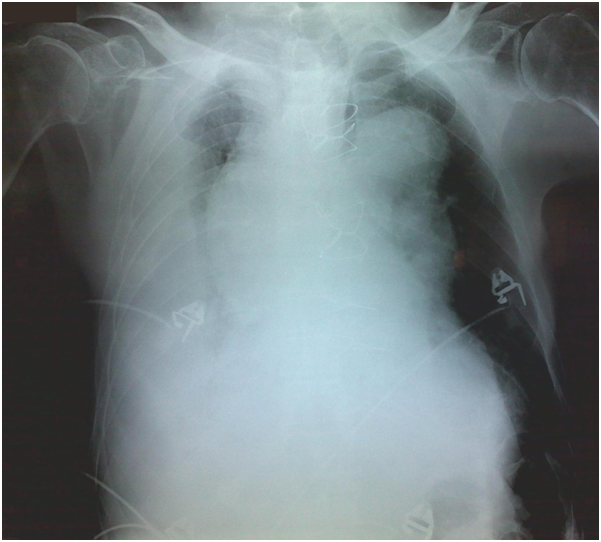

Due to patient’s history, a CT-angiography was immediately performed, which showed a massive perigraft aneurysm, 9x9.5 cm in maximum diameter, extended to the arch, compressing superior vena cava (SVC), brachiocephalic artery, right coronary artery (RCA), and graft partially detached from distal anastomosis, but within the aneurysmal sac Figure (2-7). The aneurysm was probably formed by a leakage at distal anastomosis, between the graft and the native aortic wall which was wrapped around it. A large right pleural effusion was also obvious. However, active leakage of the contrast agent from aneurysmal sac to the surrounding tissues was not observed at that point.

Figure 2 CT-angiography revealed a massive perigraft aneurysm, 9x9.5 cm. Superior vena cava compression (white arrowheads) and right pleural effusion are also manifested.

Figure 3 Extension of the aneurysm to aortic arch was detected.